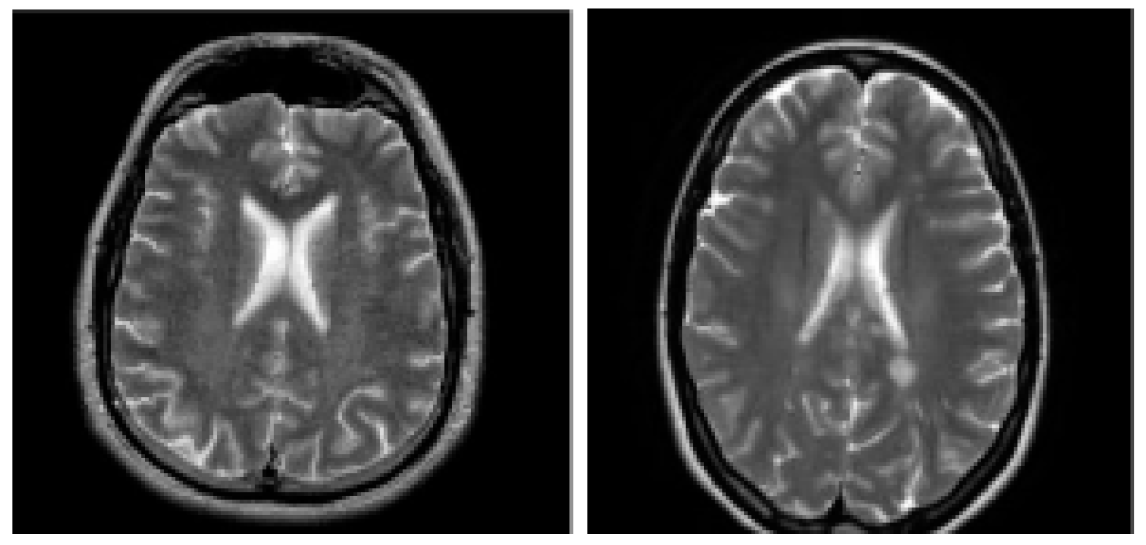

7]. The MS images were obtained from eHealth laboratory. All cases have been experienced neurologist MS identification, and confirmed by the radiologist. Samples of healthy and MS diseased brains are showed as

Figure 1.